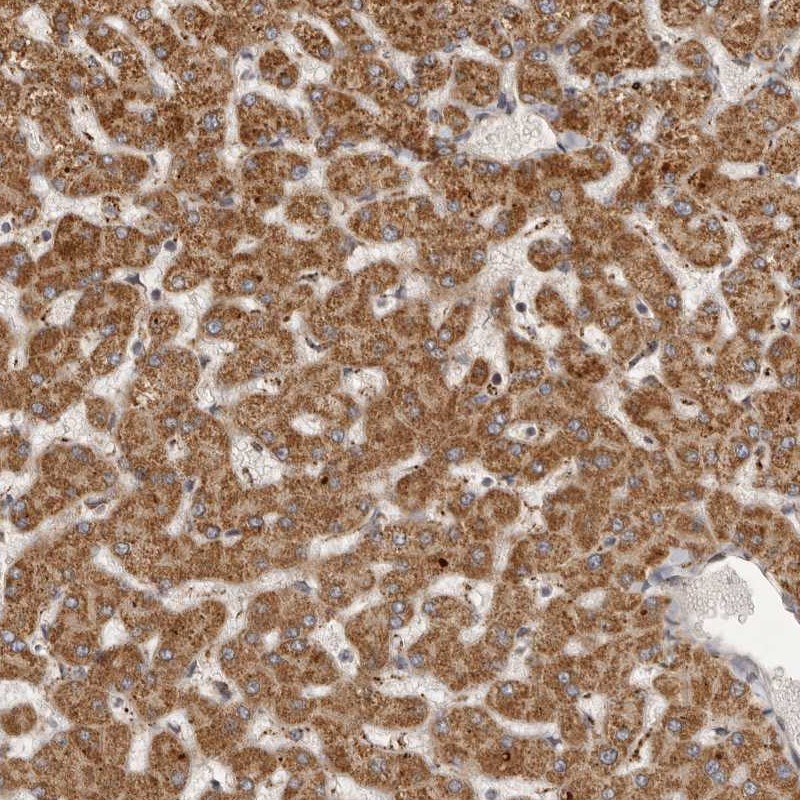

Immunohistochemical staining of human liver shows cytoplasmic positivity in hepatocytes.